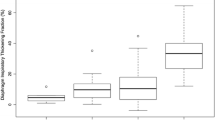

The main results are summarized in Tables 1, 2 and 3 and in Supplemental Tables 1 and 2.

Table 1 reports the agreement between what each rater observed and what was expected, across two different respiratory maneuvers and three different respiratory patterns. The error rate in detecting lung sliding and lung pulse has been also reported in Table 1.

Table 2 reports inter-rater agreement of the joint evaluation of B-mode and M-mode imaging for lung sliding and lung pulse.

Table 3 reports the intra-observer reliability of the joint assessment of B-mode and M-mode imaging for lung sliding and lung pulse.

Tidal breathing

During tidal breathing, the raters failed to recognize lung sliding in up to 42.0% of imaging and lung pulse in up to 29.2% (Table 1). Based on the integration of B-mode and M-mode imaging, inter-rater agreement was slight for lung sliding and slight to moderate for lung pulse (Cohen’s k 0.54 for rater 1 vs 2; Cohen’s k < 0.20 for rater 1 vs 3 and rater 2 vs 3; Table 2). Cohen’s k pointed out perfect or almost perfect intra-observer agreement for raters 2 and 3, for both lung sliding and lung pulse; on the other hand, only moderate intra-observer reliability for lung sliding and slight for lung pulse were found for rater 1 (Table 3). Based on B-mode imaging only, inter-rater agreement was worse for both lung sliding and lung pulse (eTable 1), while intra-observer agreement remained substantially unchanged (eTable 2).

Apnea

During apnea, inter-rater agreement was moderate for lung pulse (Table 2), while inter-rater agreement for lung sliding was moderate to perfect (Cohen’s k 1 for rater 1 vs 3; Cohen’s k 0.41 and 0.46 for rater 2 vs 3 and rater 1 vs 2, respectively; Table 2), based on the integration of B-mode and M-mode. Cohen’s k pointed out a very poor intra-observer agreement for raters 1 and 3 in detecting lung sliding and a perfect intra-observer agreement for rater 2 (Table 3). For lung pulse, a moderate to perfect intra-observer agreement was found for raters 2 and 3 and no agreement for rater 1 (Table 3). Based solely on B-mode imaging, inter-rater agreement was found to be worse while intra-observer agreement to be improved (supplemental tables).

Muller maneuver

During Muller maneuvers, lung sliding was certainly recognized in 14.9 up to 73.0% of imaging and uncertain in up to 56.2% (Table 1). Inter-rater agreement was slight to fair for both lung sliding and lung pulse (Table 2). Cohen’s k pointed out a moderate to almost perfect or perfect intra-observer agreement, for both lung sliding and lung pulse detection, all based on the integration of B-mode and M-mode imaging (Table 3).

Valsalva maneuver

During Valsalva, lung sliding was certainly recognized in up to 68.7% of imaging and uncertain in up to 31.2% (Table 1). Inter-rater agreement was slight for lung sliding and slight to moderate for lung pulse (Table 2). Cohen’s k pointed out a moderate to almost perfect intra-observer agreement for lung sliding and a substantial to perfect intra-observer agreement for lung pulse detection (Table 3).

Hyperventilation

During hyperventilation, lung sliding was erroneously unrecognized in up to 12.5% of imaging and judged uncertain in 27.1 to 35.4% of imaging by two out of three raters (Table 1). All raters failed to correctly recognize lung pulse in most imaging obtained during hyperventilation (Table 1). Inter-rater agreement was slight to fair for lung sliding and very poor for lung pulse (Table 2). Cohen’s k pointed out a wide range of intra-observer agreement among raters, from poor to perfect, both for lung sliding and lung pulse (Table 3).

Based solely on the evaluation of B-mode imaging obtained during Muller and Valsalva maneuvers and hyperventilation trials, inter-rater reliability, as well as intra-observer agreement, remained globally and substantially similar when compared to those based on the integration of B-mode and M-mode imaging, both for lung sliding and lung pulse (supplemental tables).